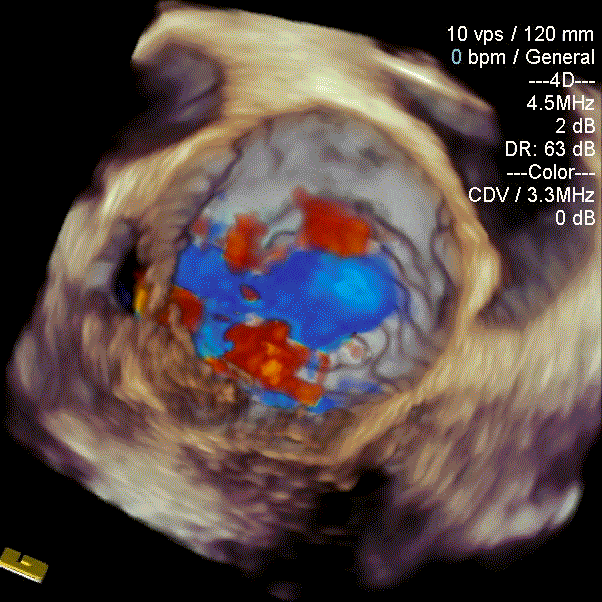

瓣中瓣植入前

二尖瓣重度反流

术后左室造影无反流